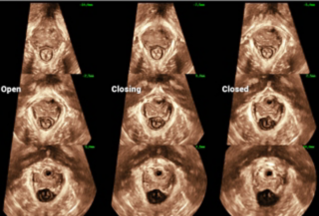

During their visit, the Southeast Asian delegation delved into in-depth discussions on the Standardized Chinese Ultrasound Training System and the Advancements in Pelvic Floor Ultrasound Technology with the experts from the West China Second Hospital of Sichuan University. These guests commended the Chinese ultrasound training system for its "remarkable reference value" and were impressed by the well-established development of pelvic ultrasound technologies in China, supported by extensive multi-center projects. Many experts also expressed their enthusiasm for future collaborations to undertake similar multi-center research projects with Mindray.